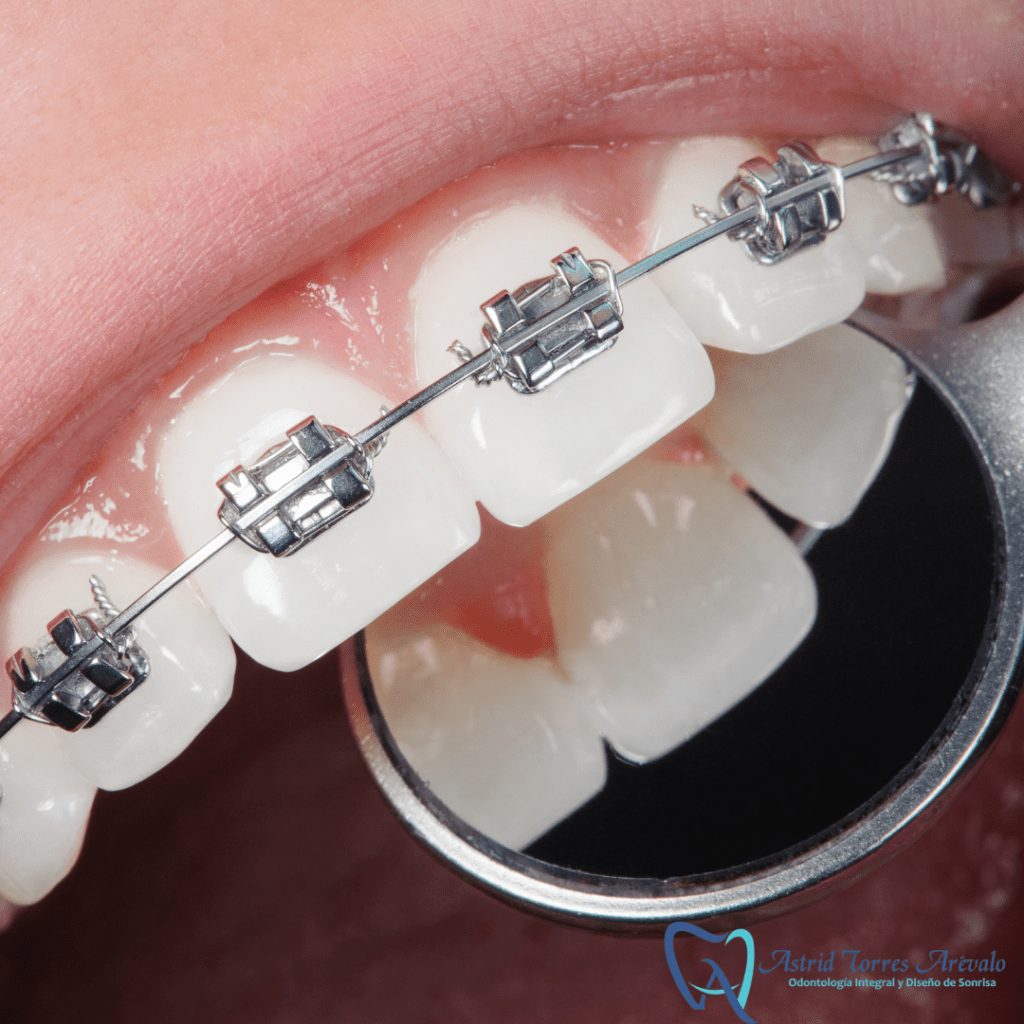

ORTODONCIA

- Ortopedia maxilar

- Ortodoncia convencional

- Ortodoncia de Auto ligado

- Ortodoncia Estética